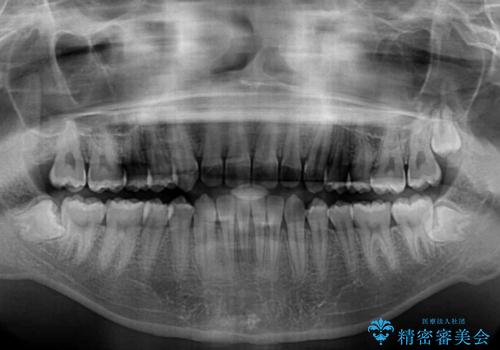

しっかり使って短期間で治療 インビザラインによる叢生解消

- 上下前歯のデコボコを気にして来院された患者様です。

高校2年生の後半であったため、受験も近く、大学に入学してからでも良いのではと提案しました。

本人の「しっかりと装着する」という強い意志があったため、来院の負担を少なく受験までに終えられるよう、インビザラインにて矯正治療を行うこととしました。

「しっかりと装着する」が実行でき、高校3年生の秋には治療を終えることができました。

入試時期に入ると、後戻り防止のリテーナー装着が疎かになる可能性があったり、リテーナーが壊れてしまった場合すぐに来院できなかったりというリスクがあったため、下顎前歯の舌側をワイヤーで固定することとしました。